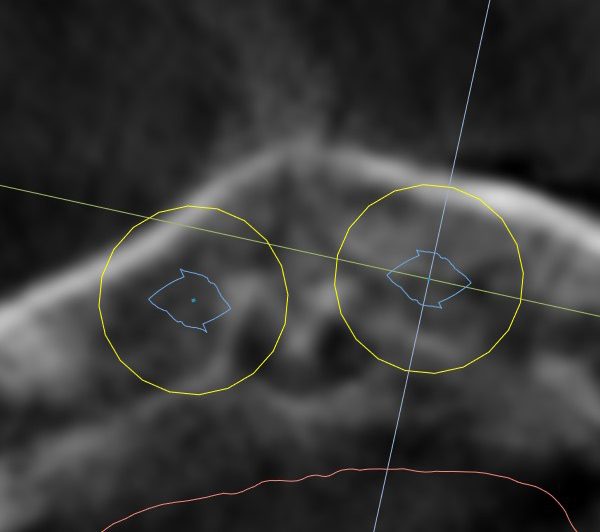

Extraction after forced eruption can allow for a much more favorable implant site compared with extraction alone. This is possible because the tension applied to the periodontal ligament during orthodontic tooth movement stimulates osteoblastic activity to induce new bone formation. As the tooth moves coronally during extrusion, soft tissue and bone attached to the periodontal fibers migrate in the same direction. As a result, forced eruption can be used to enhance the quality and quantity of both hard and soft tissue of future implant sites.

The special report presented below illustrates how orthodontic extrusion was successfully used to improve the periodontal architecture prior to the placement of two adjacent implants in the esthetic zone and thus allowed for a more ideal restorative result.